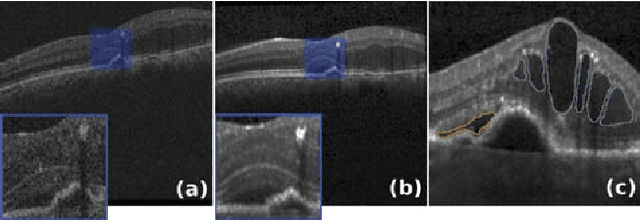

Abstract:Segmenting anatomical structures such as the photoreceptor layer in retinal optical coherence tomography (OCT) scans is challenging in pathological scenarios. Supervised deep learning models trained with standard loss functions are usually able to characterize only the most common disease appeareance from a training set, resulting in suboptimal performance and poor generalization when dealing with unseen lesions. In this paper we propose to overcome this limitation by means of an augmented target loss function framework. We introduce a novel amplified-target loss that explicitly penalizes errors within the central area of the input images, based on the observation that most of the challenging disease appeareance is usually located in this area. We experimentally validated our approach using a data set with OCT scans of patients with macular diseases. We observe increased performance compared to the models that use only the standard losses. Our proposed loss function strongly supports the segmentation model to better distinguish photoreceptors in highly pathological scenarios.

Abstract:Optical coherence tomography (OCT) has become the most important imaging modality in ophthalmology. A substantial amount of research has recently been devoted to the development of machine learning (ML) models for the identification and quantification of pathological features in OCT images. Among the several sources of variability the ML models have to deal with, a major factor is the acquisition device, which can limit the ML model's generalizability. In this paper, we propose to reduce the image variability across different OCT devices (Spectralis and Cirrus) by using CycleGAN, an unsupervised unpaired image transformation algorithm. The usefulness of this approach is evaluated in the setting of retinal fluid segmentation, namely intraretinal cystoid fluid (IRC) and subretinal fluid (SRF). First, we train a segmentation model on images acquired with a source OCT device. Then we evaluate the model on (1) source, (2) target and (3) transformed versions of the target OCT images. The presented transformation strategy shows an F1 score of 0.4 (0.51) for IRC (SRF) segmentations. Compared with traditional transformation approaches, this means an F1 score gain of 0.2 (0.12).